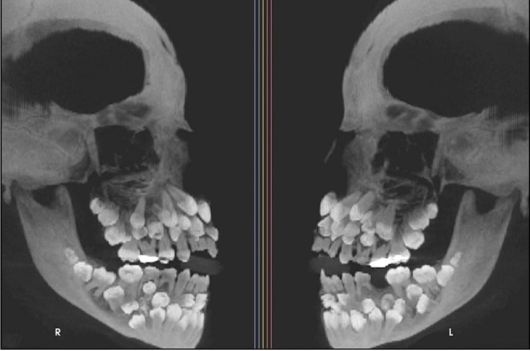

브라질의 한 소녀 입 안에서 치아 81개가 발견됐다./미국 치과교정·악안면외과학회지 |

최근 VN익스프레스 등에 따르면 브라질에 사는 11세 소녀의 구강 엑스레이 결과 입 안에서 유치 18개와 영구치 32개, 과잉치 31개 등 총 81개 치아가 발견됐다.

이는 ‘다발성 과잉치증(multiple hyperdontia)’으로 일반적으로 성인 기준 32개인 정상 치아 수를 넘는 추가 치아가 다수 존재하는 선천성 이상이다. 보통은 1~2개의 과잉치가 발견되며, 이번처럼 30개가 넘는 과잉치가 확인된 사례는 전 세계적으로도 매우 드물다.

소녀의 사례는 브라질 미나스제라이스주 주이스지포라 연방대학교 치과병원 연구팀이 진료 중 확인한 뒤 미국 치과교정·악안면외과학회지에 보고됐다.